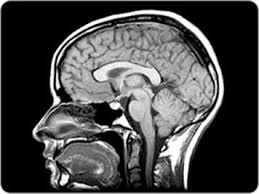

Anatomy of the brain on mri, caudate nucleus, lentiform nucleus, thalamus, ventricles radiology of brain tumors can be found elsewhere on this site, as well as brain tumor mimics. The anatomy of the brain is studied by means of axial, coronal and sagittal views. The brain, contained in and protected by the skull and suspended in cerebrospinal fluid, is one of the most important and complex organs in the body. Radiology department, rijnland hospital leiderdorp, the netherlands.